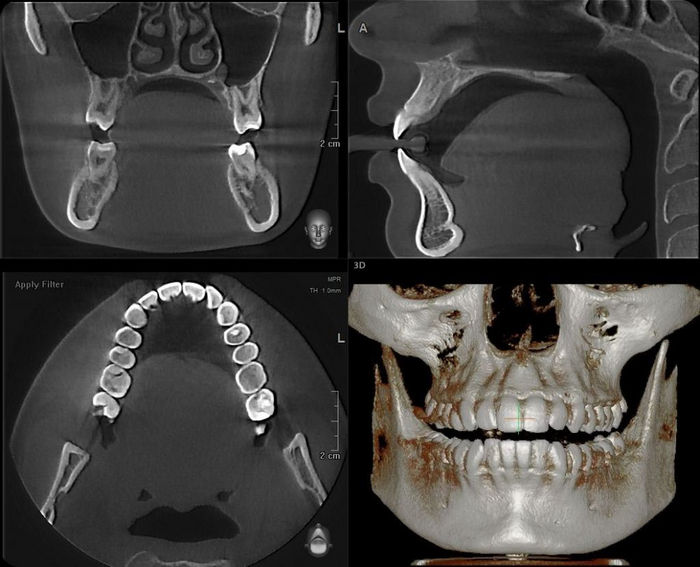

Компью́терная томогра́фия — метод неразрушающего послойного исследования внутреннего строения предмета( в данном случае тушки пациента)…..Метод основан на измерении и сложной компьютерной обработке разности ослабления рентгеновского излучения различными по плотности тканями. Короче говоря, чем дольше луч проходит через ткани, чем слабее он становится и разницу между слоями улавливает датчик, после чего специальная программа эти слои нарезает, позволяя увидеть тушку в трехмерном пространстве. Короче, мы сможем повертеть нужный нам участок со всех сторон.

Панорамный снимок- двухмерный

Компьютерная томография- трехмерный

Как вы уже догадались при получении двухмерного изображения трехмерного объекта, его структуры будут накладываться друг на друга. Так как рентген-диагностика заключается в анализе разницы плотности слоев, что выражается на снимках в виде различных оттенков серого, то более плотные слои(белые) могут запросто перекрывать менее плотные(черные), из-за чего точность этой диагностики снижается.

Компьютерная томография «нарезает» объект послойно, позволяя увидеть все структуры под каким угодно углом без искажений. Таким образом мы сможет поставить максимально точный диагноз, определить более точный прогноз зуба, определить расположение будущих и уже установленных имплантатов, определить расположение гайморовой пазухи и нижнего альвеолярного нерва при удалении сложных зубов, определить расположение корней, определить количество каналов в корнях….можно продолжать долго.

Вот ещё примеры.

Поэтому если физрук сказал лыжи в апреле, значит лыжи стоматолог направляет на КТ, то идем на КТ, даже если надо решать вопрос с одним зубом

Некоторые изображения выли взять из статьи Fabio Gorni «CBCT: The dark side of the moon» (styleitaliano), которая была переведена при поддержке компании STOMWEB